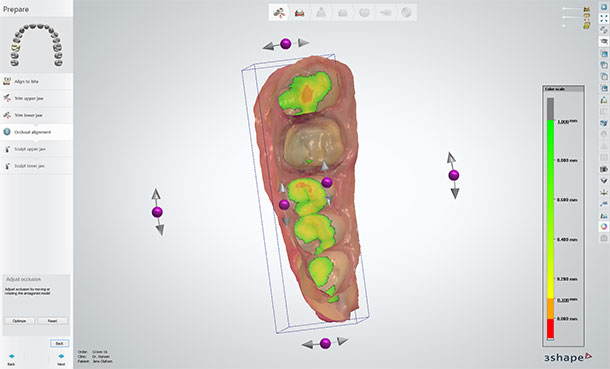

1.4 Check the static occlusion of the bite scan

The dentist will often have controlled static occlusion himself in his TRIOS system. However, it should be verified in the lab before designing because you will not have a model to control static occlusion later on. Realign the bite if needed.

1.8 Apply Dynamic Virtual Articulation

Since we are working without a model, you must always control dynamic occlusion using the software Virtual Articulator. You will not have a model to place in a physical articulator.

Check dynamic occlusion in the software

1.9 Virtual Articulation – Adapt Design and check contact points

Press the “Adapt Design” button to remove material that obstructs smooth dynamic occlusion. Naturally, you end with checking your occlusal contact points.